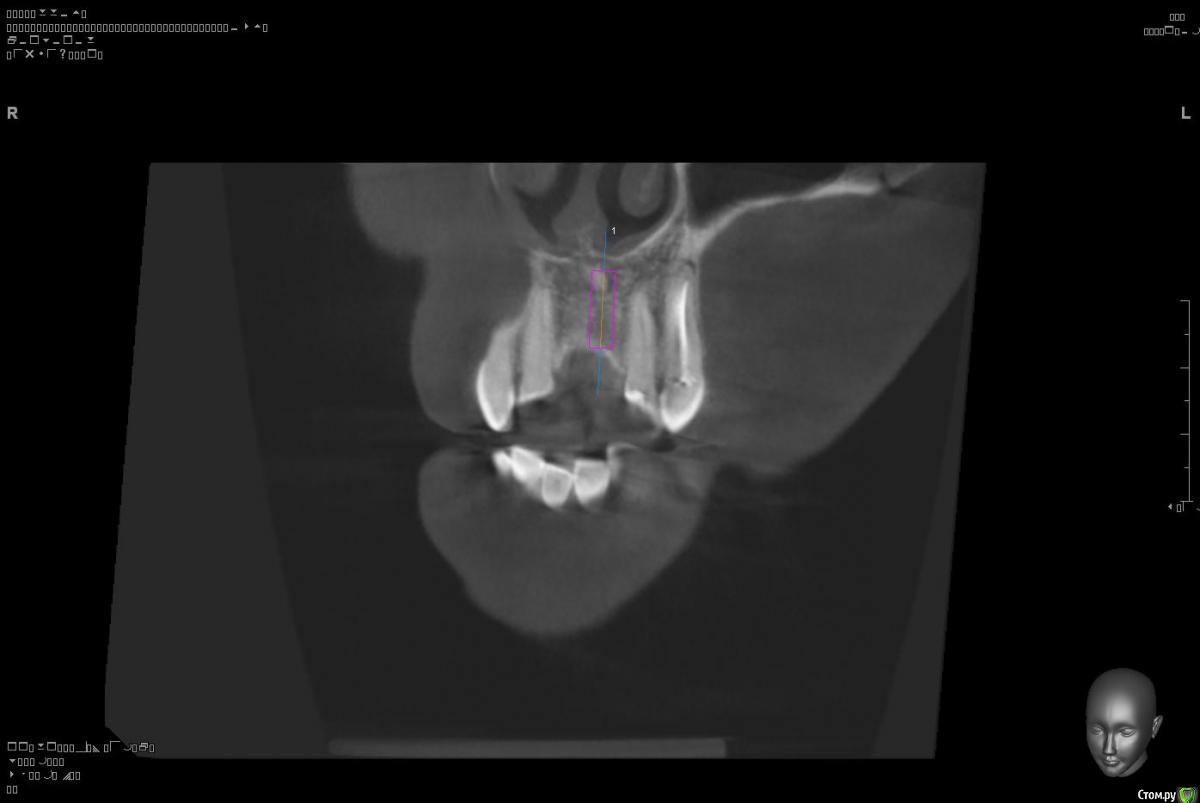

Platon Опубликовано 10 января, 2016 Поделиться Опубликовано 10 января, 2016 Здравствуйте.Помогите с планированием начинающему.Пациентка 38 лет. отсутствует 21. визуально в области 21 провал (фото нет, пока только кт). ходит с акриловой "птичкой"ортопед говорит: ставь, она к эстетике не будет предъявлять претензий))). с чем мне не хочется соглашаться(система ALPHA BIOкак правильно поступить?какие варианты рассматриваю:1. имплантация 3,75 на 11.5 SPI. ,+ временная коронка. Без какой либо пластики.2. костная пластика (мембрана,ксено,) без имплантации, сст, капа на 4 -6мес. потом имплантация + временная коронка3. имплантация, сст , временная коронка С учетом обстановки, прессинга, отсутствия опыта в аугментации, склоняюсь к третьему варианту. заранее спасибо за советы!удачного дня! Ссылка на комментарий

Platon Опубликовано 31 января, 2016 Автор Поделиться Опубликовано 31 января, 2016 Продолжение.не судите строго за фото, первый раз вообще фоткаю операцию)спасибо за советы.По порядку. После того, что мне написали, я решил все -таки уговорить на конусный имплантат (3.7-11.5 ImplantDirect). Также ортопед не хотел делать временную коронку, сказал что сделает каппу, птичку в топку -тоже сделали. Слизистая в области 21 была в рубцах. Исходя из этого всего я решил, коль временной коронки не будет, то сст подсаживать тоже не стану пока,(ортопеда уговаривал сделать временную коронку)))- торк был хороший 35-50н) для того чтобы сст попрактиковаться, но(((.в итоге, анестезия, разрез, сверло пилотное и сверло 2.2, далее расщепление с помощью набора майзенгер с использованием спредеров до нужного диаметра, установил имплантат, торк контролируемый, можно было подобрать любой) в итоге оставил 35. заглушка, совсем немного ксено, мембрана, ушился. ждем. Будет что-то типо каппы которая слегка отдавливает десну,формируя сосочки. не знаю, ни разу такую еще не видел.планирую на этапе раскрытия все-таки сст и временную коронку увидеть.вот. через 4 мес. выложу, что получилось) Если есть советы, критика, всему буду рад, спасибо 3 Ссылка на комментарий

St_Klaus Опубликовано 1 февраля, 2016 Поделиться Опубликовано 1 февраля, 2016 взять 11,5 не заглублять данный имплант, оставить 1,5 мм супракрестально., если позволяет десна, чтобы уменьшить ремоделинг кости. Соглашусь, альфа не предназначена для заглубления, если не ошибаюсь, даже производители не рекомендуют.Если есть советы, критика, всему буду рад, спасибоВсе хорошо, только чуть более небно бы вывел платформу, хотя бы 0,5 мм Ссылка на комментарий